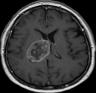

Machine learning has been widely adopted for medical image analysis in recent years given its promising performance in image segmentation and classification tasks. The success of machine learning, in particular supervised learning, depends on the availability of manually annotated datasets. For medical imaging applications, such annotated datasets are not easy to acquire, it takes a substantial amount of time and resource to curate an annotated medical image set. In this paper, we propose an efficient annotation framework for brain MR images that can suggest informative sample images for human experts to annotate. We evaluate the framework on two different brain image analysis tasks, namely brain tumour segmentation and whole brain segmentation. Experiments show that for brain tumour segmentation task on the BraTS 2019 dataset, training a segmentation model with only 7% suggestively annotated image samples can achieve a performance comparable to that of training on the full dataset. For whole brain segmentation on the MALC dataset, training with 42% suggestively annotated image samples can achieve a comparable performance to training on the full dataset. The proposed framework demonstrates a promising way to save manual annotation cost and improve data efficiency in medical imaging applications.

翻译:近年来,由于在图像分割和分类任务方面表现良好,医学图像分析广泛采用了机器学习。机器学习的成功,特别是监督学习的成功,取决于手动附加说明数据集的可用性。对于医疗成像应用来说,这种附加说明数据集不容易获得,需要大量的时间和资源来翻译附加说明的医学成像集。在本文件中,我们建议为大脑MR图像建立一个高效的注释框架,为人类专家提供信息性样图像,供人类专家作说明。我们评估了两种不同的大脑图像分析任务的框架,即脑肿瘤分割和整个大脑分割。实验显示,对于BRATS 2019数据集的脑肿瘤分割任务,培训一个只有7%的附加说明图像样本的分解模型,其性能与全数据集培训的性能相当。对于MALC数据集的整个大脑分割,用42%的附加说明性图像样本进行的培训,可以实现与全数据集培训的类似性能。拟议的框架展示了节省人工注解成本和提高医疗成像应用数据效率的有希望的方法。